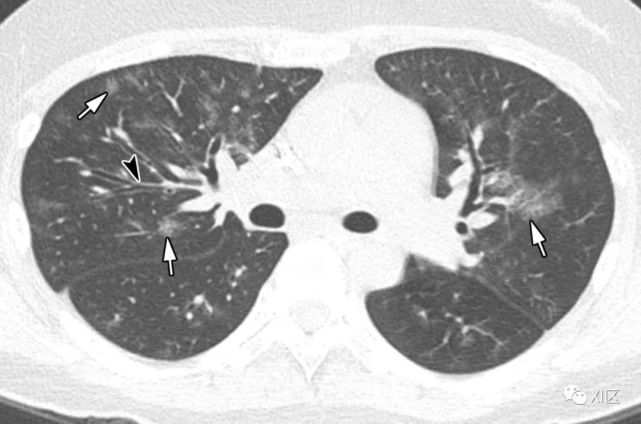

图26 51岁的急性髓细胞性白血病患者,因鼻病毒引起的肺炎,在骨髓移植后3个月出现呼吸困难。

(a)最初的胸部X线照片显示两个肺部均出现不规则的,不明确的斑片状不透明性增加(箭头)。 (b,c)同一天在较低气管水平(b)和两个较低肺叶基底节段(c)上获得的轴向CT图像显示不透明区域不透明,小叶间隔增厚(箭头)和不明确的斑块状GGO( 箭头)。

51岁急性髓系白血病患者,骨髓移植后3个月出现呼吸困难,因鼻病毒引起肺炎。(上) 最初的胸片显示两肺不规则的模糊斑片状不透明度增加(箭头)。在同一天的较低气管水平(中)和两肺下叶基底段(下)轴位向CT图像显示两肺不规则的不透明度增加区域,肺小叶间隔增厚(箭头)和不明确的斑状GGO(箭头)。

Koo H J , Lim S , Choe J , et al. Radiographic and CT Features of Viral Pneumonia[J]. Radiographics, 2018, 38(3):719-739.